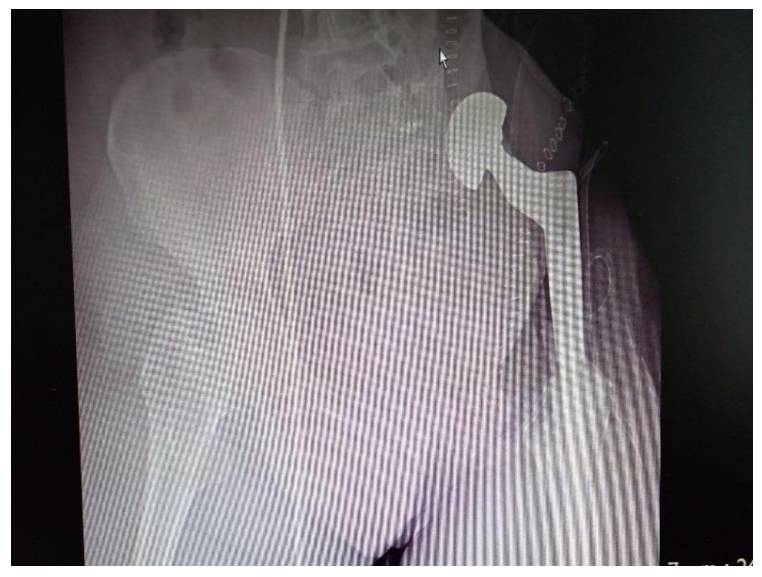

Post-operative: X-ray shows hip transposition with prosthesis after internal hemipelvectomy.